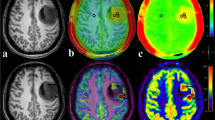

Representative examples for four different tumour types of structural MRIs and CEST maps (shown in Fig. 2a) and Z-Spectra (shown in Fig. 2b) show a cystic component present in the IDH-wild-type with reduced signal in the FS CEST maps in the amide and amine ranges (Fig. 2a, IDH-wild-type); minor differences between AB and FS maps in the solid tumour, more evident in IDH-mutant_1p/1qret and in the amine range (Fig. 2a). Fig. 3 shows the MTRasym (Fig. 3a–c) and the ∆MTRasym spectra (Fig. 3d–f) for the different tumour subtypes (two glioma groups in Fig. 3a and d; three glioma groups in Fig. 3b and e; four glioma groups in Fig. 3c and f). Both the MTRasym and the ∆MTRasym spectra showed different contributions from the amide and the amine regions between glioma subtypes over the frequency range analyzed. The average MTRasym spectrum in the NAWM over all patients was null at a frequency of ~ 3 ppm from the water resonance (Fig. 3a).

Representative examples of structural MRI, CEST maps, and Z-spectra. a Representative structural MRI and CEST maps for IDH-wild-type, IDH-mutant_1p/19qret with and without AB/FS mismatch, and IDH-mutant_1p/19qcodel. AB_APTw indicates the asymmetry-based metric while FS_APTw is the fluid-suppressed metric. ∆3.5 is the 1-ppm offset range centred at the amide offset of 3.5 ppm, while ∆2 is the 1-ppm offset range centred at the amine offset of 2 ppm. b Representative Z-spectra of the cyst component and of the tumour core for the same tumour types